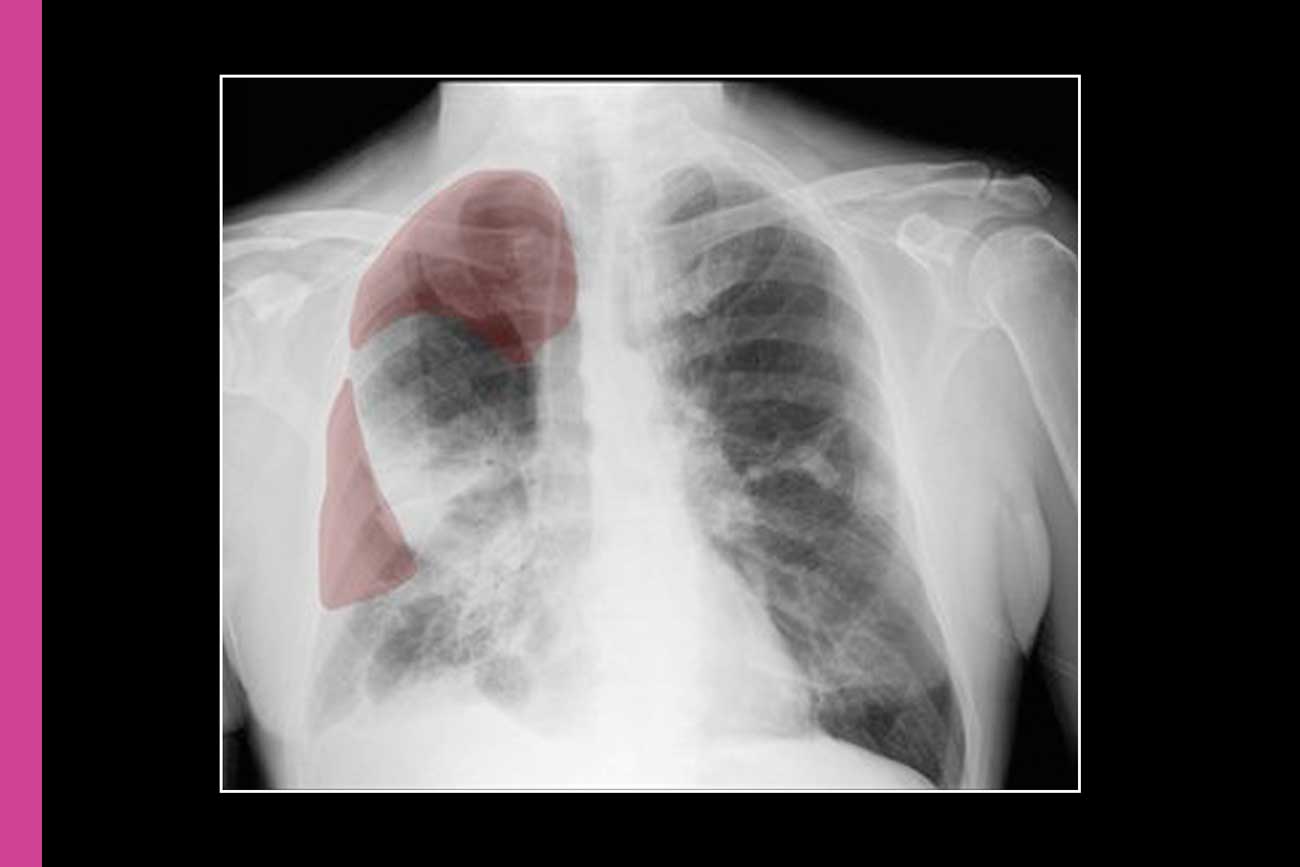

Tens of thousands of Americans suffer pneumothoraces, a type of collapsed lung, annually. The condition is caused by trauma or lung disease — and serious cases can be deadly if diagnosed late or left untreated.

This type of collapsed lung is difficult to identify: The illness can mimic others both in symptoms and in x-rays, in which only subtle clues may indicate its presence. Meanwhile, radiologists must interpret hundreds of images daily, and some hospitals do not have around-the-clock radiologists.

UCSF researchers created the first AI bedside program to help flag potential cases to radiologists. In 2019, the tool was the first AI innovation of its kind to be licensed by the U.S. Food and Drug Administration. Today, it’s used in thousands of GE Healthcare machines around the world.

Researchers from the Department of Radiology and Biomedical Imaging created a database of thousands of anonymous chest X-rays. Some of these images showed cases of collapsed lungs and others not. Next, researchers trained the AI tool on this database before testing it on thousands of other images to ensure it could flag potential cases accurately.

The AI screener works with portable X-ray machines, so doctors can use it right at a patient’s bedside without making major infrastructure investments.